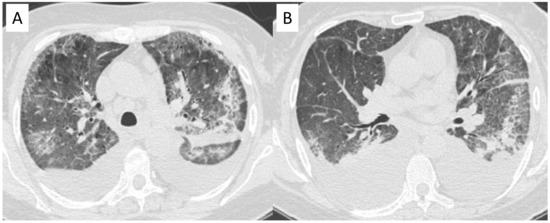

2.5. Eosinophilic Granulomatosis with Polyangiitis (EGPA-Churg-Strauss)

| EGPA | Migrant GGOs, transient consolidation, irregular bronchial wall thickening, small nodules with peribronchial and centrilobular distribution, pleural effusion. |